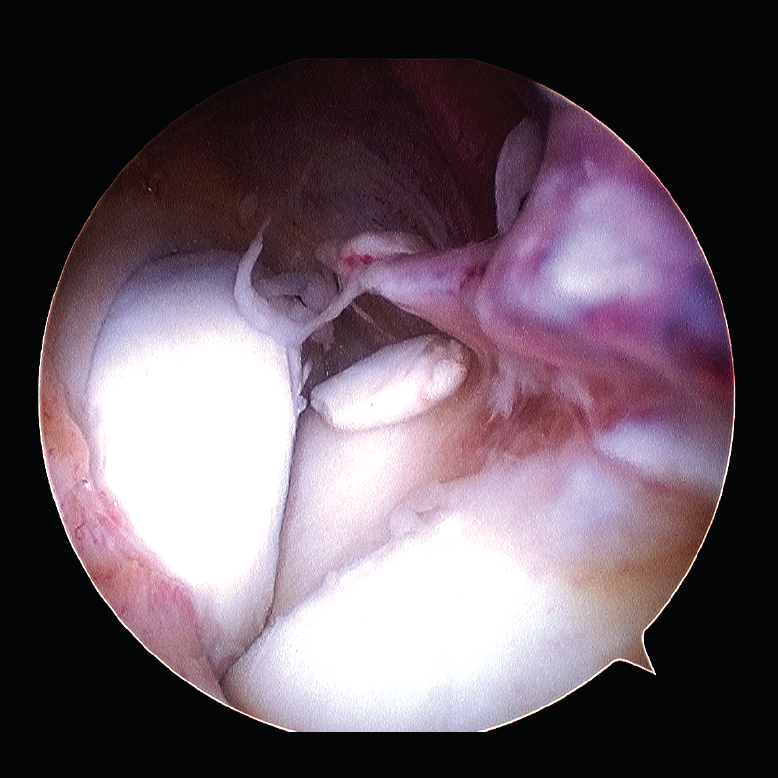

Las patologías más habituales tratadas por medio de una artrolisis artroscópica incluyen: la sinovectomía parcial, el desbridamiento intraarticular de adherencias o lesiones condrales y la liberación capsular y/o capsulotomía anterior y posterior. Los cuerpos libres se pueden extraer y también resecar los osteofitos, frecuentemente situados en coronoides, olécranon o en la foseta olecraneana humeral (Figura 4).

Figura 4. Exéresis de cuerpos libres articulares por artroscopia.